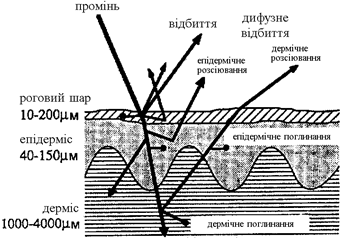

Промені, що проникають в тканину, частково поглинаються, частково розсіюються і частково пропускаються (рисунок 1.2).

Рисунок 1.2 - Оптичні властивості лазерного променя на шкірі

В залежності від довжини хвилі випромінювання, що падає, відбивається до 60% випромінювання. Розсіювання залежить від негомогенних структур тканини і визначається різними показниками заломлення в різних шарах і різницею між шарами і їх навколишнім середовищем. Хвилі з довжиною набагато більшою, ніж діаметр шару (³ 10 мкм), розсіюються клітинними структурами лише в незначній мірі. Але тому, що електромагнітний спектр широко використовуваних лазерів простягається від ІЧ (1 мм-0,78 мкм) до УФ (0,38-0,10 мкм) діапазону довжин хвиль, ми практично завжди маємо справу з розсіюванням. Глибину проникнення для довжини хвиль більше 1,0 мкм можна розрахувати на основі закону Ламберта-Бера в першому наближенні [7].

Розсіювання в біологічній тканині залежить від довжини хвилі лазерного променя. Випромінювання ексимерного лазера УФ діапазону (193, 248, 308 і 351 мкм), а також ІЧ-випромінювання 2,9 мкм ErYAG-лазера і 10,6 мкм СО2-лазеру мають глибину проникнення від 1 до 20 мкм [10,11]. Тут розсіювання грає другорядну роль. Для світла з довжиною хвилі 450-590 нм, що відповідає лініям аргону, глибина проникнення складає в середньому 0,5-2,5мм. Як поглинання так і розсіювання грають тут значну роль. Лазерний промінь цієї довжини хвилі хоча і залишається в тканині колімованим у центрі, але він оточений зоною з високим розсіюванням. Від 15% до 40% енергії падаючого пучка світла розсіюється. У області спектра між 590 і 1500 нм, у яку входять лінії Nd:YAG лазера 1,06 і 1,32 мкм, домінує розсіювання. Глибина проникнення складає від 2,0 до 8,0 мм.